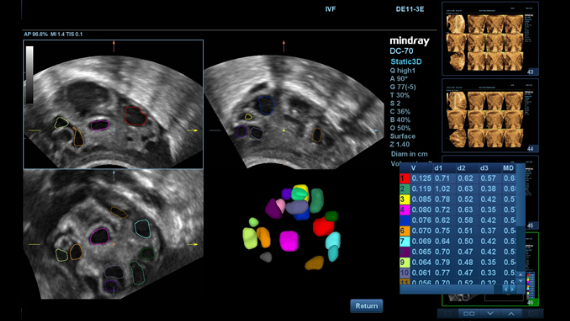

Imagens clĂnicas